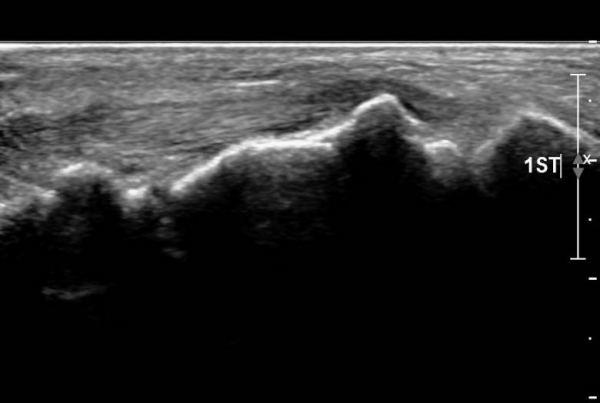

ÃÊÀ½ÆÄ ¼Ò°ß :  Àü°æ°ñ°Ç Á¾´Ü¸é°Ë»ç¿¡¼­ Àü°æ°ñ°ÇÀÌ °í¿¡ÄÚ¼¶À¯È­(hyperechoic fibrillar pattern) ¾ç»óÀ¸·Î °üÂûµÇ´Âµ¥

¼³Çü°ñ ºÎÂûºÎ¿¡¼­ °æ¹ÌÇÑ Á¦¿¡ÄÚ ¾ç»óÀÌ °üÂûµÈ´Ù(»çÁø 1, 2).